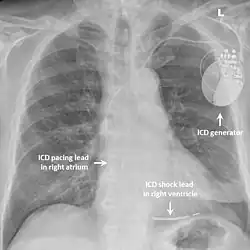

La quinidine prolonge l'intervalle QT et réduit la susceptibilité ventriculaire à un trouble rythmique[13],[14], et semble efficace dans la prévention de ces derniers[15]. Les antiarythmiques de la classe IC (dont flécaïne) ou III (amiodarone) n'ont pas prouvé d'efficacité[16]. La pose d'une défibrillateur automatique implantable peut être discuté. Le réglage de ce dernier reste délicat devant un nombre important de chocs inappropriés[3], et prône aux interférences avec l'onde T, plus ample[17].